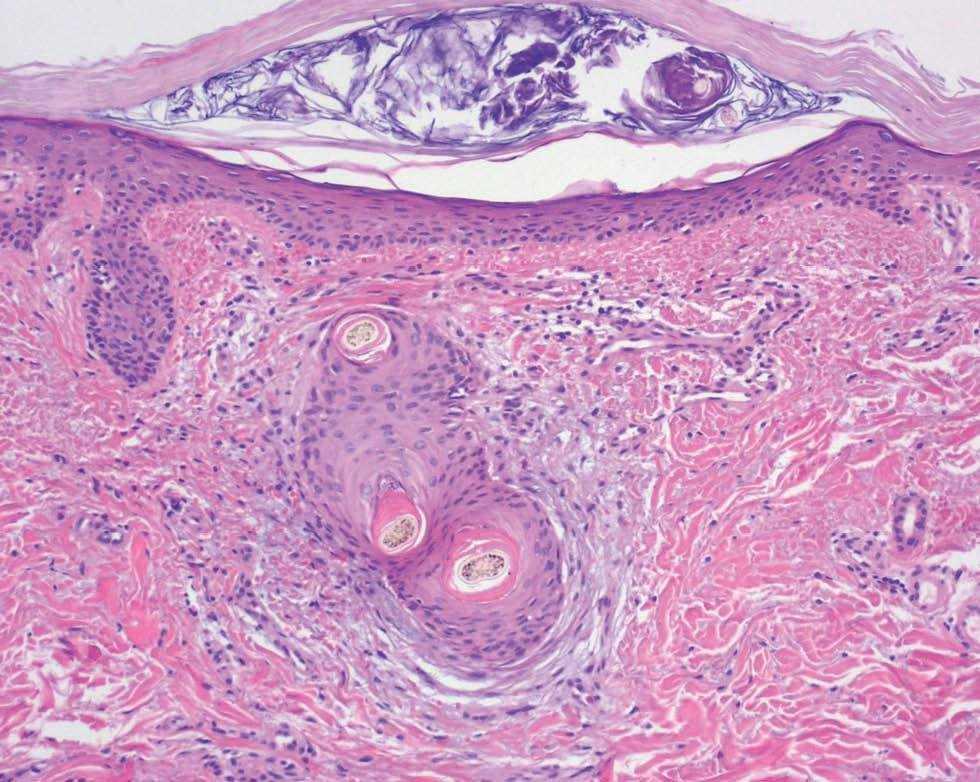

Varón de 48 años, sin antecedentes personales ni familiares de interés, que presentaba cuadro de diarrea crónica de más de un año de evolución y síndrome general, con astenia, anorexia y adelgazamiento de más de 15 kg de peso que le confería un aspecto caquético, con poliadenopatías de 2-3 cm de diámetro, elásticas y no adheridas a planos profundos en cuello, axilas y región inguinal. Posteriormente, desarrolló un cuadro de demencia subcortical, con cambios en el comportamiento, déficit de memoria, ataxia y hemiparesia IV/V derecha. En la exploración cutánea se observaron encías edematosas que sangraban con facilidad (fig. 1), lesiones purpúricas en piernas, de predominio folicular (fig. 2), así como descamación cutánea generalizada ictiosiforme (fig. 3). En las pruebas complementarias destacaban hemoglobina 9,2 g/dl; volumen corpuscular medio 100 fl; 2.500 leucocitos con fórmula normal; velocidad de sedimentación globular 55 mm y datos de malnutrición severa con prealbúmina 8 mg/dl (normal 10-40) y retinol 1,3 mg/dl (normal 3-6); vitamina B12 171 pcg/ml (normal 211-911), ácido fólico 0,5 ng/ml (normal > 1,6); niveles séricos de ácido ascórbico 7 micromol/l (normal 20-80 micromol/l); enzima conversora de angiotensina 71,3 U/l (normal 8-55); proteinograma con Ig M < 30 mg/dl; serologías hepatitis B, C, lúes y virus de la inmunodeficiencia humana, negativas; coprocultivos y parásitos en heces, negativos; bacilos ácido-alcohol resistentes en esputo y orina, negativos; Mantoux 0 mm; bioquímica y recuento celular de líquido cefalorraquídeo normal; radiografía de tórax normal; resonancia magnética nuclear cerebral con áreas extensas de desmielinización de sustancia blanca supra e infratentorial. Se realizó endoscopia del tubo digestivo con estudio anatomopatológico, observando a nivel del estómago gastritis crónica activa y la presencia de granulomas epitelioides no necrotizantes a nivel del duodeno, colon e íleon, sin observarse bacilos ácido-alcohol resistentes. La biopsia de un ganglio linfático axilar demostró una linfoadenitis granulomatosa no necrotizante. El estudio histológico de las lesiones purpúricas de las piernas mostró folículos pilosos con hiperqueratosis folicular y discreta hemorragia perifolicular (fig. 4). En la biopsia de lesiones de piel de tórax se observó una epidermis ligeramente adelgazada con hiperqueratosis de apariencia laminar sin paraqueratosis y atenuación de la capa granulosa (fig. 5). Con todos estos datos inicialmente se estableció el diagnóstico de enfermedad granulomatosa idiopática generalizada (probable sarcoidosis) y se instauró tratamiento corticoideo oral, con escasa mejoría del cuadro clínico. Posteriormente, ante la escasa respuesta al tratamiento, se revisaron todas las biopsias, y aunque no se encontraron macrófagos PAS positivos en las mismas, se enviaron muestras de biopsia duodenal, sangre y líquido cefalorraquídeo para la determinación de fragmentos genómicos de Tropheryma whippelii mediante reacción en cadena de la polimerasa (PCR) y para microscopía electrónica, que fueron positivos en las muestras duodenales. Ante estos resultados se estableció el diagnóstico de enfermedad de Whipple, forma granulomatosa pseudosarcoidótica, con malabsorción intestinal secundaria que condicionó cuadro de malnutrición extrema, escorbuto, ictiosis adquirida y anemia megaloblástica. Se instauró tratamiento con imipenem más estreptomicina durante 15 días, seguido de trimetropim-sulfametoxazol, así como complejos vitamínicos con vitamina C y vitamina B12. A las pocas semanas se produjo una completa resolución de las lesiones cutáneas y de la diarrea, así como ganancia de 10 kg de peso. En el control gastroscópico al mes del tratamiento no se observaron lesiones macro ni microscópicas. A pesar de completar el tratamiento durante dos años el paciente sólo presentó discreta mejoría desde el punto de vista neurológico.

Fig. 4.--Pelos retorcidos, hiperqueratosis folicular y extravasación hemática (hematoxilina-eosina, 200).